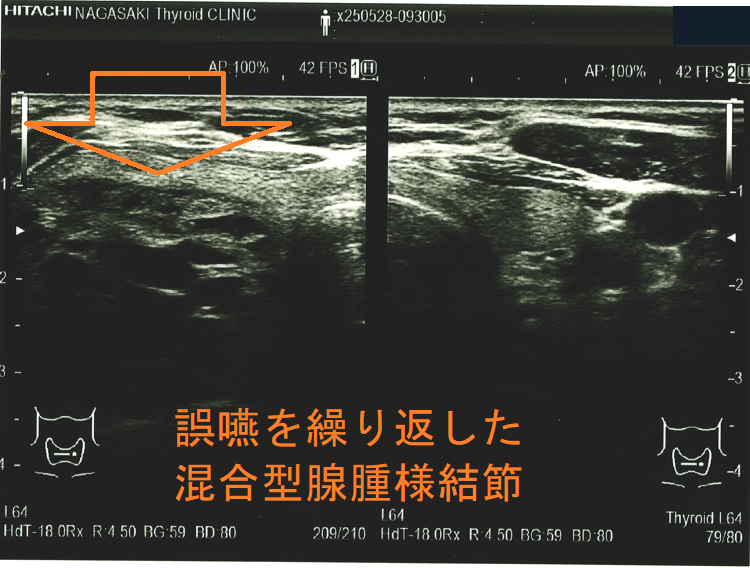

胸骨下まで伸びた巨大甲状腺腫による食道圧迫は、嚥下障害と食道咽頭逆流を生じ、誤嚥性肺炎の原因になります(Korean J Intern Med. 2016 Nov;31(6):1196-1197.)

誤嚥を繰り返した混合型腺腫様結節